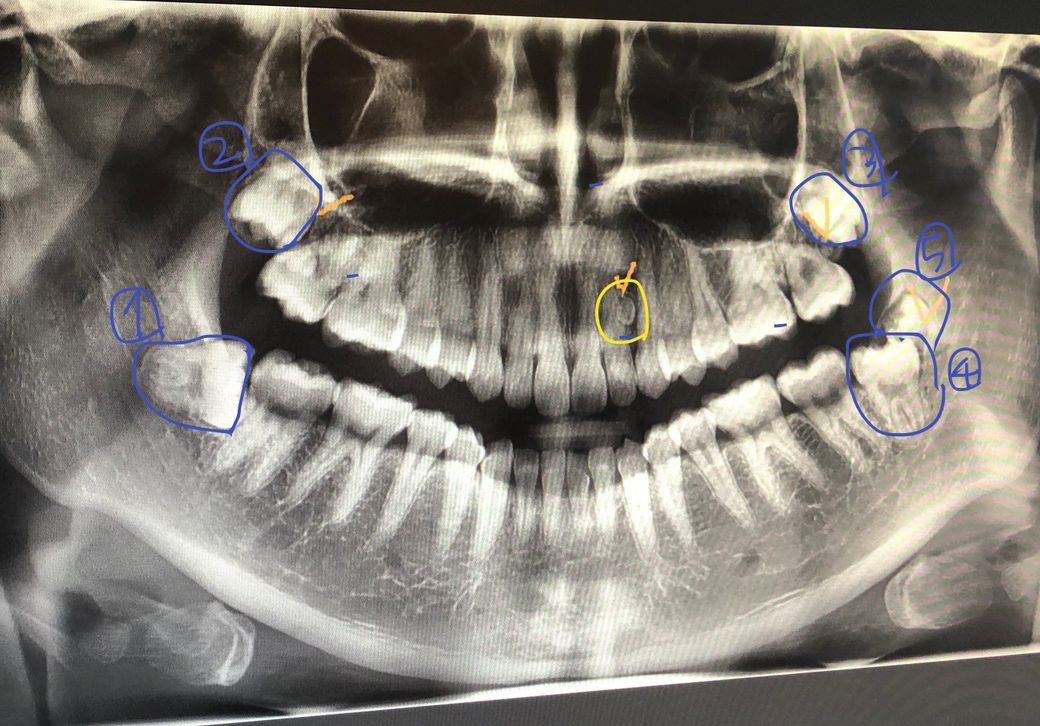

사진상 오른쪽 아래에 보시면 4번에 사랑니가 하나있고 5번에 과잉치가 있어요ㅠ 한쪽에 빼야할 이가 두개나 있는데 이거 발치난이도 어떤가요? 뺄때 많이 아플까요?

아래 사랑니 2개와 사랑니 뒤에 있는 과잉치는 수술을 통해 빼 주어야 합니다. 그리고 위의 각각 사랑니는 조금 더 기다리면 내려올 것으로 보이니 조금 더 내려온 다음에 뽑는 것이 좋습니다.

오른쪽 아래 사랑니가 다른곳에 비해서 난이도가 있을꺼 같습니다. 위쪽 사랑니는 뽑는건 어렵지 않지만, 입을 벌리시는게 힘드실수도 있습니다.

왼쪽아래 사랑니와 과잉치는 깊게 있지도 않기 때문에 그렇게 어려워 보이지는 않습니다.

뺄때 잇몸수술을 해야 하기 때문에 일반 발치보다 불편감이 있을수 있어요.